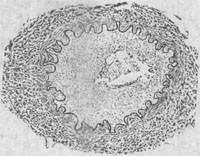

2.脑动脉炎 患者多为儿童,亦可为青壮年。患者常在急性期症状消失后1~5月出现偏瘫和失语等症状。主要病变是脑底多发性动脉炎及其所引起的脑实质损害。病变主要累及脑底动脉各干支,以大脑中动脉及大脑前动脉病变最重,大脑后动脉次之。病变呈跳跃性节段性分布,使该动脉粗细不匀、僵直或呈灰白色绳索状。此外,在基底节及其邻近脑实质内可见毛细血管及小静脉明显扩张充血,有的聚集成簇。镜下见受累动脉早期可为全动脉炎,较晚期则主要为增生性动脉内膜炎,使内膜显著增厚,可引起血管腔狭窄甚至闭塞,偶尔可并发血栓形成(图18-25)。脑实质可因缺血而发生轻重不一和不同部位的水肿出血和多发性软化灶。

图18-25 钩端螺旋体病后发症——脑动脉炎模式图动脉内膜高度增生变厚,管腔变狭窄